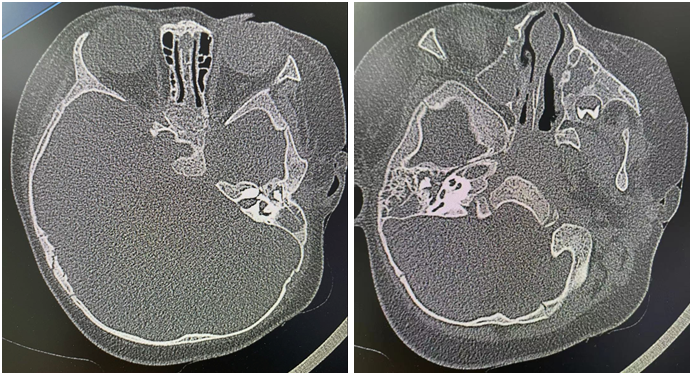

豆豆住院后,李萍采集了她耳道中的脓性分泌物进行细菌培养及药敏试验,以找出最适合治疗这种感染的抗生素。通过乳突CT检查,李萍发现豆豆右耳的中耳及乳突也充满脓性物。

“通过病史、症状、体征及辅助检查,明确了急性化脓性中耳炎的诊断,也就是说豆豆左耳鼓膜穿孔了,脓液从中耳通过穿孔处流到耳道,而且双侧中耳均有感染,如不及时治疗,右耳也可能穿孔流脓。”李萍说。